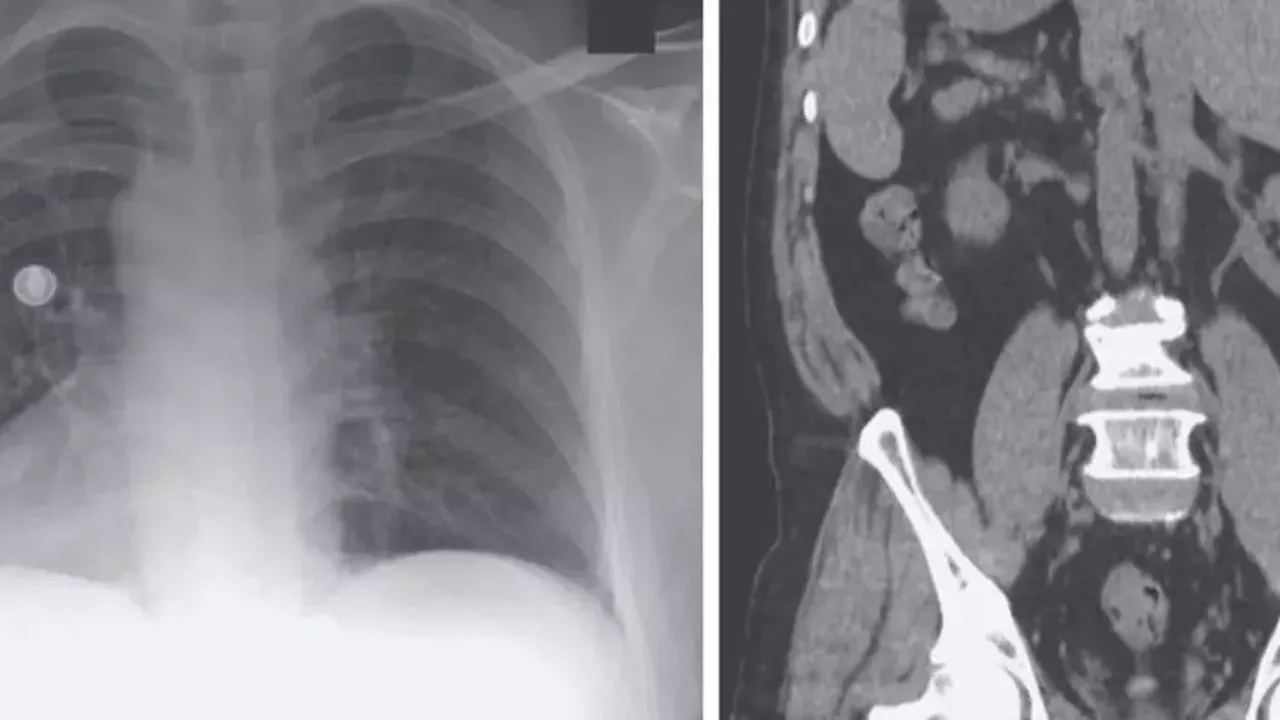

Son olarak Gaziantep Şehir Hastanesi'ne başvuran Evin Aslan'ın hastanede yapılan tetkikler sonucunda iç organlarının tamamının ters tarafta olduğu anlaşıldı. Kalp, mide, dalağı, göğüs ve karın bölgesinin sağında, karaciğer ve safra kesesinin ise solda olduğunu öğrenen Aslan, hayatının şokunu yaşadı. Mide ağrısı rahatsızlığı şikayetiyle şehir hastanesine başvuran Aslan'ı muayene eden Gastroenteroloji Uzmanı Dr. Ahmet Akbay, Aslan'ın kalbinin sağda ve diğer bütün iç organlarının ters tarafa olduğunu tespit etti.

İç organlarının tamamının ters tarafta olduğunu öğrenen Aslan, safra kanalındaki taşlar nedeniyle çektiği ağrılardan kurtulmak için ameliyat olmaya karar verdi. Aslan'ın yıllarca çektiği tüm acılar ve ağrılar, Gaziantep Şehir Hastanesi'nde yapılan başarılı ameliyat sonucu son buldu. Meslek hayatında ilk kez böyle bir durum ile karşılaştığını belirten Gastroenteroloji Uzmanı Dr. Ahmet Akbay, "Hastamız karın ağrısı şikayetiyle hastanemize başvurdu. Çekmiş olduğumuz MR'da karın iç organlarının tam tersi yerleşmiş olduğunu gördük. Bu duruma ‘situs inversus totalis' denilmektedir. Sağda olması gereken karaciğer ve safra kesesi sol tarafa ve solda olması gereken kalp ise sağ tarafa yerleşmişti. Bu hastamızda safra kanalında taş olup akut pankreatitleri geçirmekteydi. Hastamızın safra kanalındaki taşlarını ileri endoskopik yöntem olan RCP işlemiyle başarılı bir şekilde yaptık" dedi.

Tıp literatüründe çok fazla gözükmeyen bir olayla karşılaştıklarını belirten Akbay, "Bu durum dünyada ve Türkiye'de çok nadir görülen bir durumdur. Hem organların ters tarafta olması aynı zamanda safra kanalında taş ve pankreatitleri geçirmesi çok nadir görülen bir durumdur. Dolayısıyla ileri endoskopik yöntem olan RCP işlemi içinde hastanın tam ters pozisyonda, odanın dizaynını ona göre ayarladık, işlem oldukça zor olmasına rağmen başarılı bir şekilde işlemimizi yaptık, hastamız sağlığına kavuştu" şeklinde konuştu.